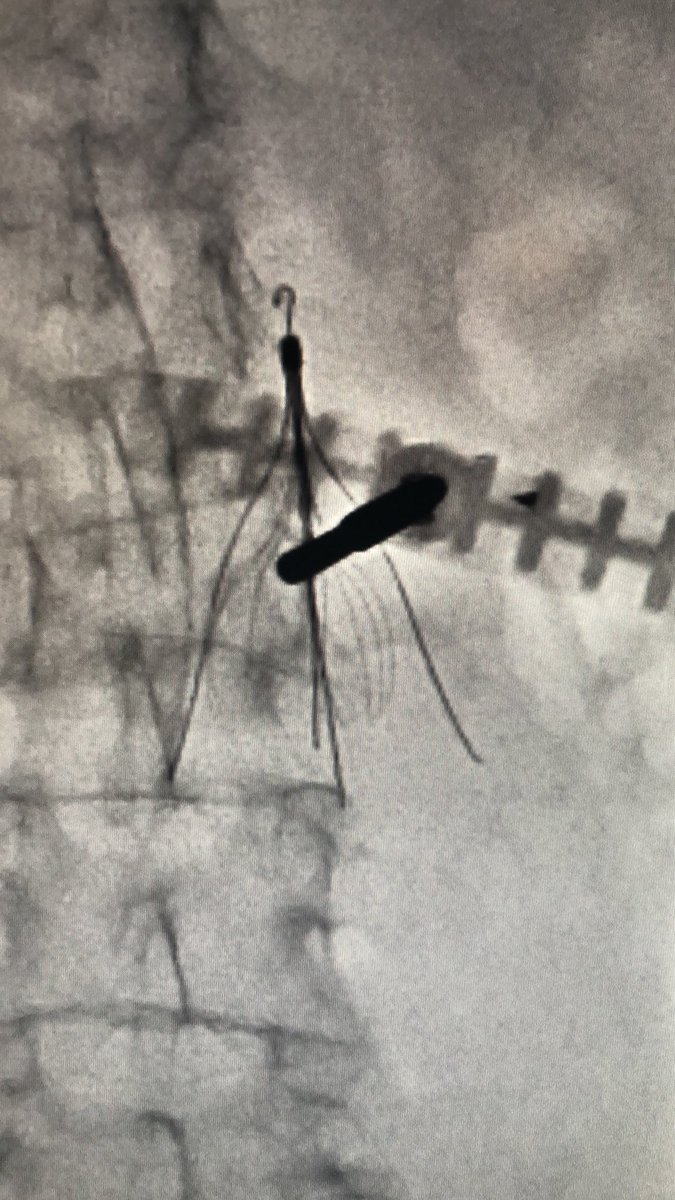

The rare #IVCFilter #Gunsight #Kyphoplasty technique. #iRad